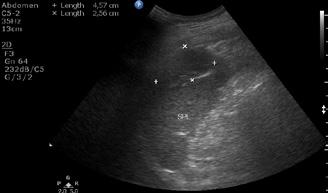

A opera sau a nu opera? Raspunsul ecografistului

Dr. Dan Adrian Stănescu 24